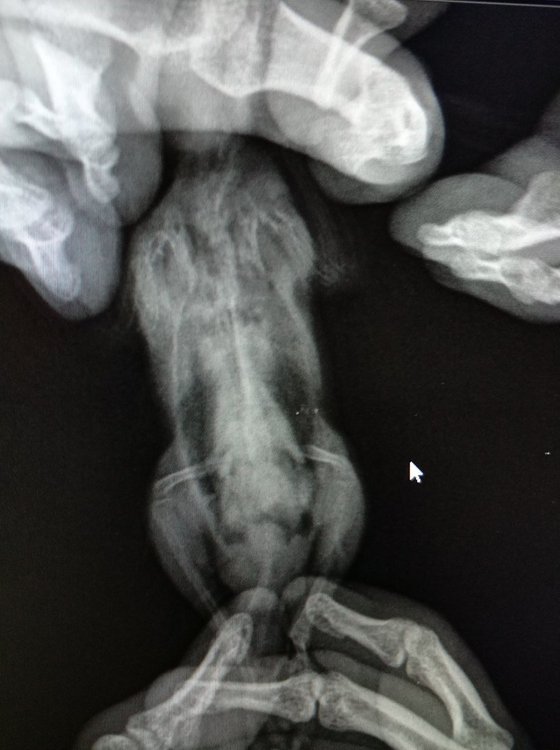

На следующий день поехали к орнитологу. Он не очень опытен (могу ошибаться, но он об этом говорил), а лучше я не нашел в городе. Он его пощупал, сделали рентген. Он сказал что с птицей все хорошо (за зрение ничего даже не сказал и не посмотрел), прописал следующее:

2. Гептрал\гепатовет (По рентгену сказал что печень плотно выглядит и надо давать это).